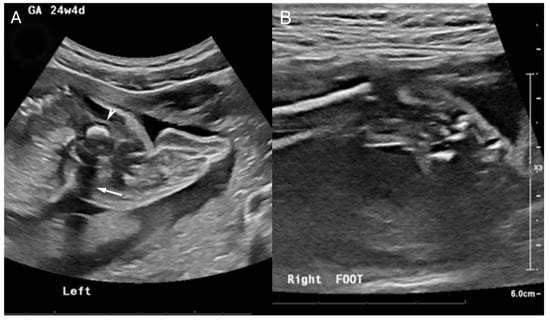

2.1. Case 1

2.2. Case 2